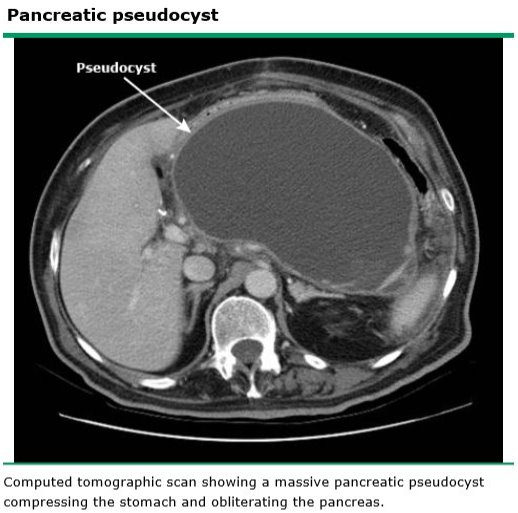

Pancreatic pseudocysts are most commonly associated with which condition?

Chronic pancreatitis

What is the treatment for pancreatic pseudocyst?

Expectant management for 3 months

[Most will resolve on their own. Those that don’t resolve will have time to mature if cystogastrostomy is required]